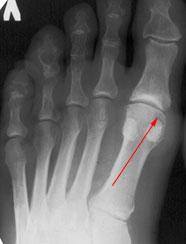

Для диагностики обязательно необходимо провести рентгенографию стопы. Этот метод позволяет выявить костные изменения, разрастания, пограничные дефекты суставных поверхностей, уменьшение суставных щелей, субхондральный склероз костной ткани и наличия кистовидных образований, что дает возможность провести дифференциальную диагностику.

На второй степени проявляется усиленный болевой синдром, которое ограничивает тыльное сгибание (разгибание) I пальца. Рентгенография выявляет субхондральный склероз, уплощение суставных поверхностей и сужение суставного пространства.